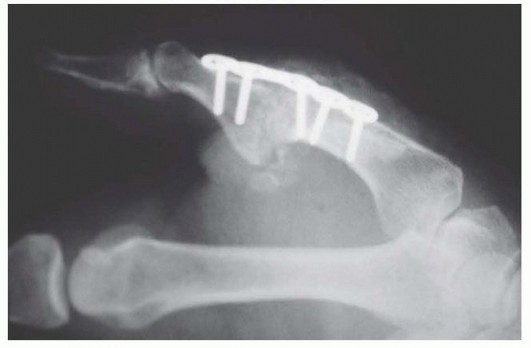

PLATE AND SCREW FIXATION

It may be desirable to use plate and screw fixation rather than cannulated screws in such cases as nonunion after attempted arthrodesis; failure of implant arthroplasty; and traumatic injuries with severe deformity, bone loss, or segmental defects (TECH FIG 6).The advantage of plates and screws is that more rigid, secure fixation can be achieved immediately, avoiding the concern for rotation or loosening around a single cannulated screw.The disadvantage of that technique is that hardware prominence and tendon irritation and adhesions are more often a source of subsequent trouble.If plate and screw fixation is chosen as the desired technique, then the overall approach and bone preparation are similar to that described for the cannulated screw technique.With the arthrodesis site reduced and temporarily stabilized with a Kirschner wire, a 2.0-mm, five-hole compression plate is contoured to the dorsal surface of the bones.The plate is first secured distally and then applied proximally using compression technique principles.It is critical to avoid long screws and irritation of the flexor pollicis longus.Closure and postoperative care are similar to that described earlier. TECH FIG 6 • Arthrodesis with plate and screw fixation.